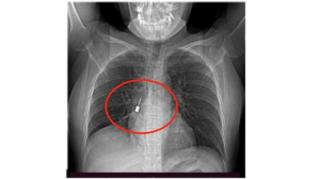

Tosse e dolore al petto: la TAC rivela qualcosa di assurdo nel polmone

Una giovane donna calabrese ha vissuto un’esperienza tanto insolita quanto pericolosa, arrivando al pronto soccorso del Grande Ospedale Metropolitano di Reggio Calabria con tosse insistente e forti al torace. Solo attraverso una Tac i